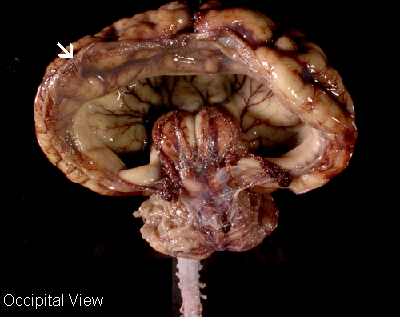

Holoprosencephaly: Note that the occipital half of the brain is reduced to a thin and transparent glial-ependymal seam (arrow).